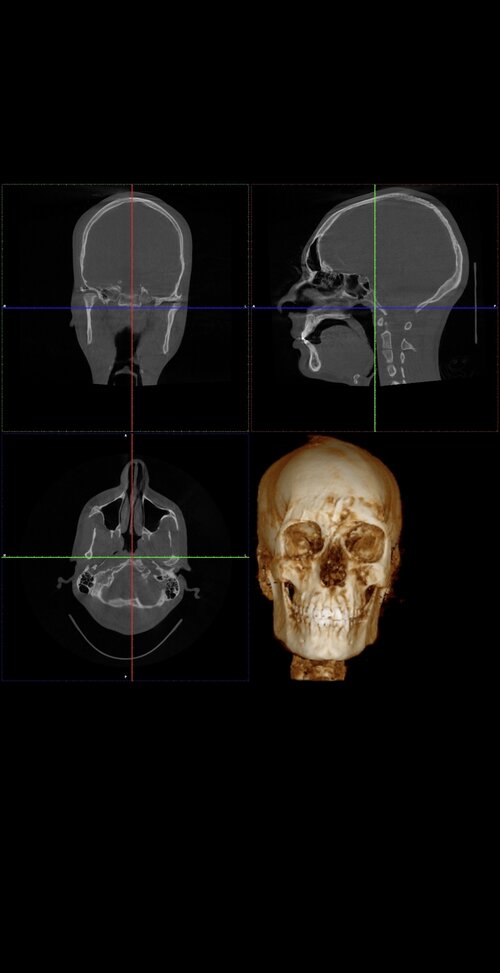

Ct scan for reference

Your mandible is recessed and your airway oropharynx cross section looks very small. Just imagine when you relax and lay down, your tongue goes back and blocks your airway even more.

Get a sleep study (preferably type 1 or 2, type 3 is bad) and consult a maxillofacial surgeon

The philtrum seems quite tall in the ct which may explain why your teeth show less. You have room for advancement in both jaws

Yes. Your lower front teeth are inclined forward